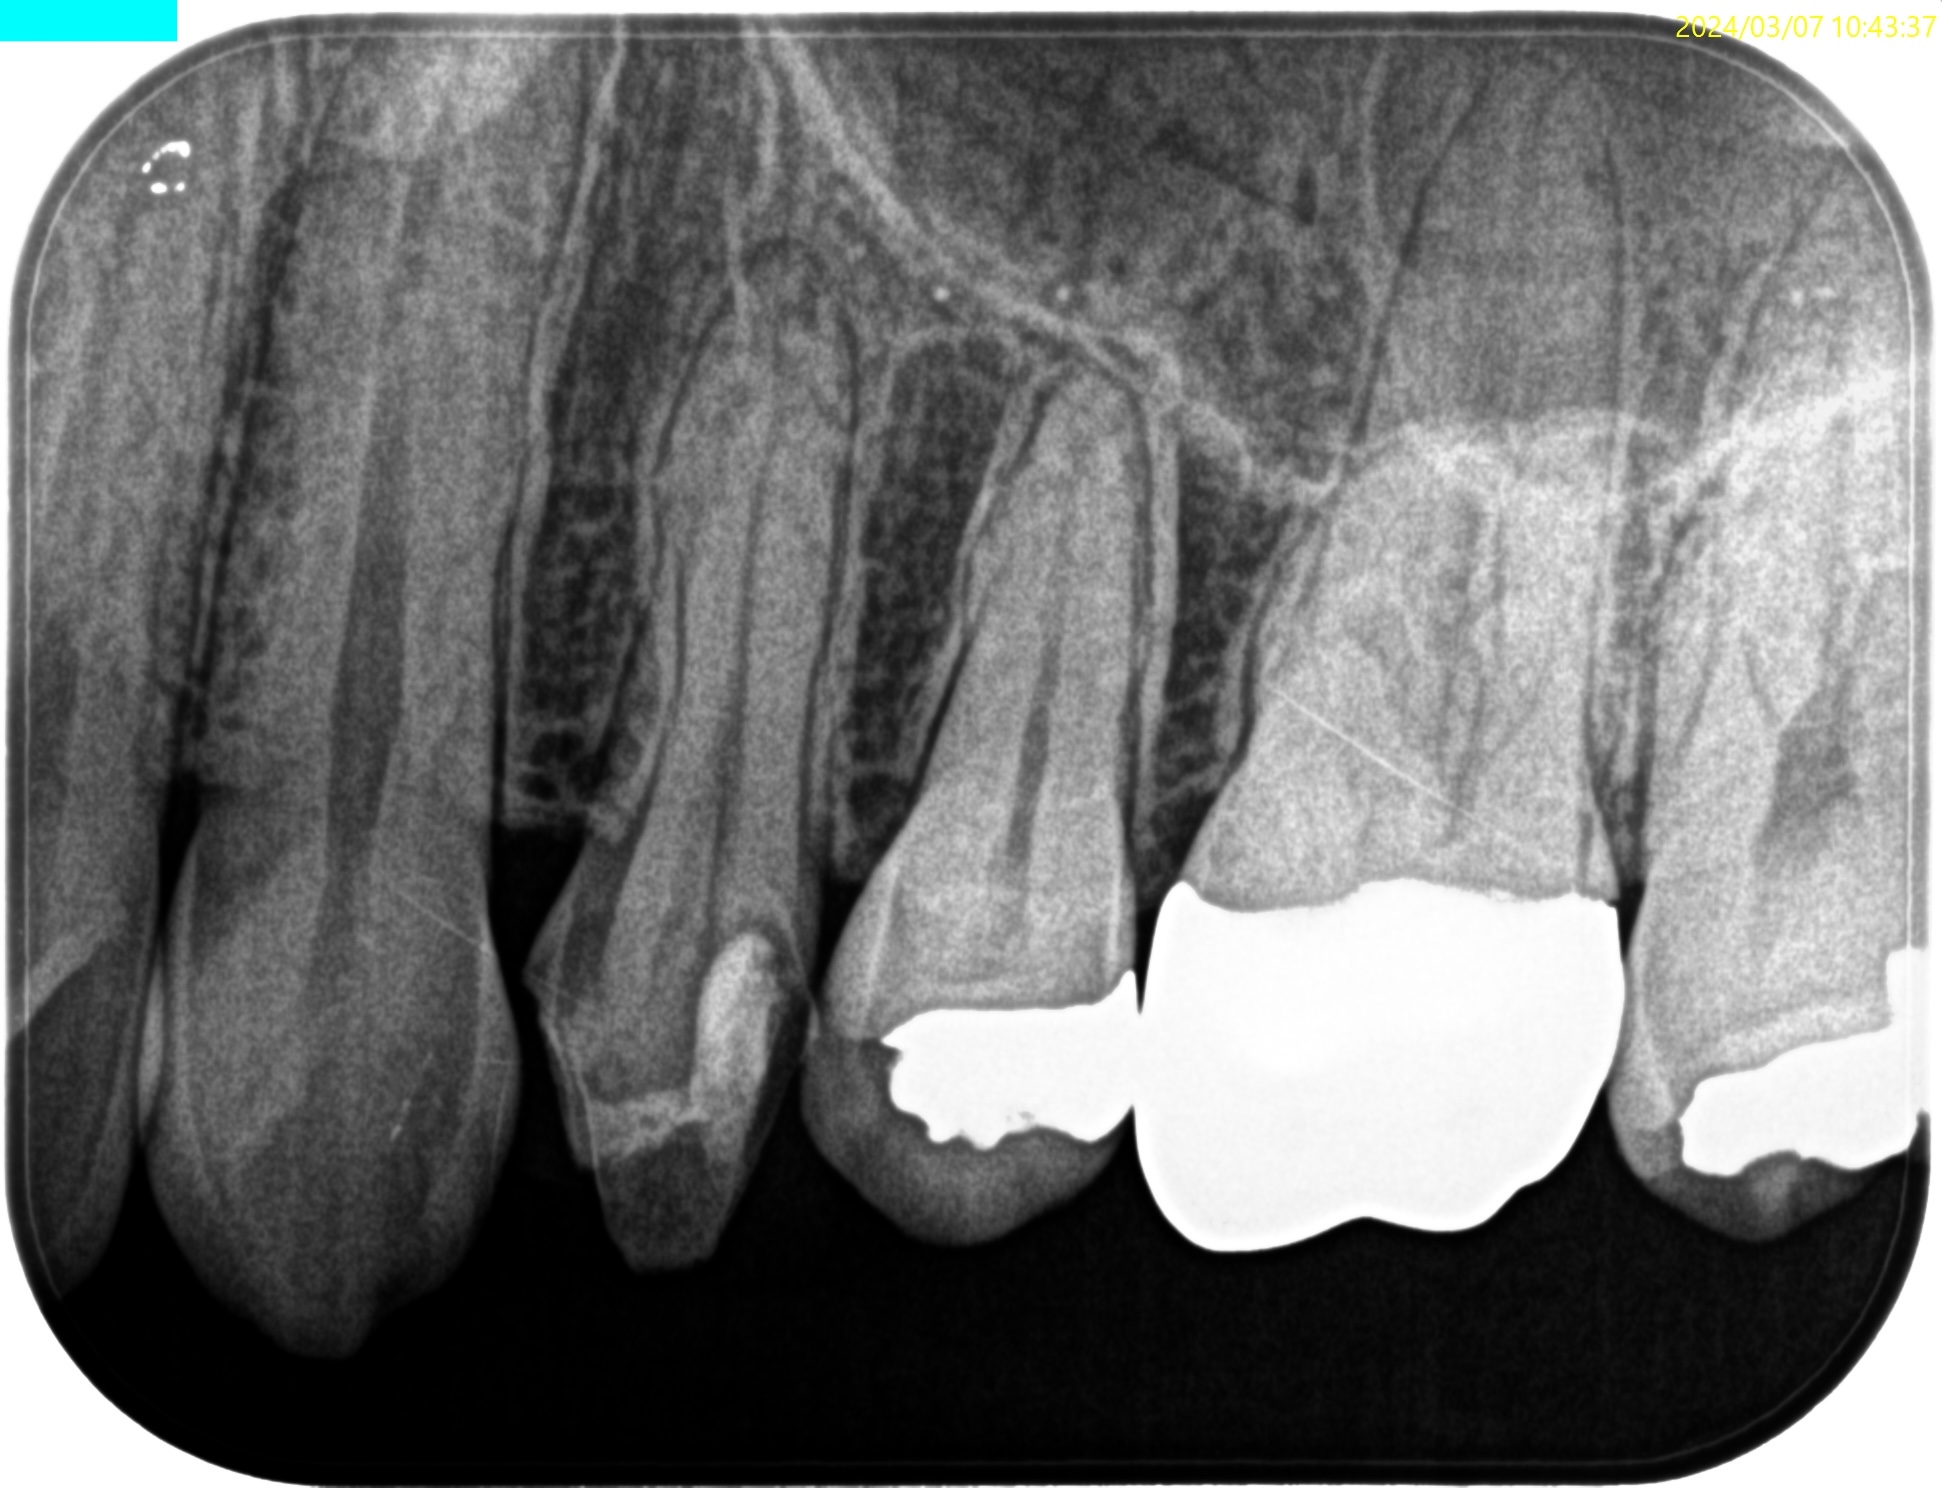

Pre-op Endo Test(2024.3.7)

#12 Cold++1/13, Perc.(+), Palp.(-), BT(-), Perio Probe(WNL), Mobility(WNL)

Pulp Dx: Pulp necrosis

Periapical Dx: Symptomatic apical periodontitis

Recommended Tx: RCT

#12はMTAセメントという魔法の薬で神経を保護したので大丈夫ですよ、と言われたそうだが

神経を保護するような治療を行うと、歯髄が石灰化してしまう。